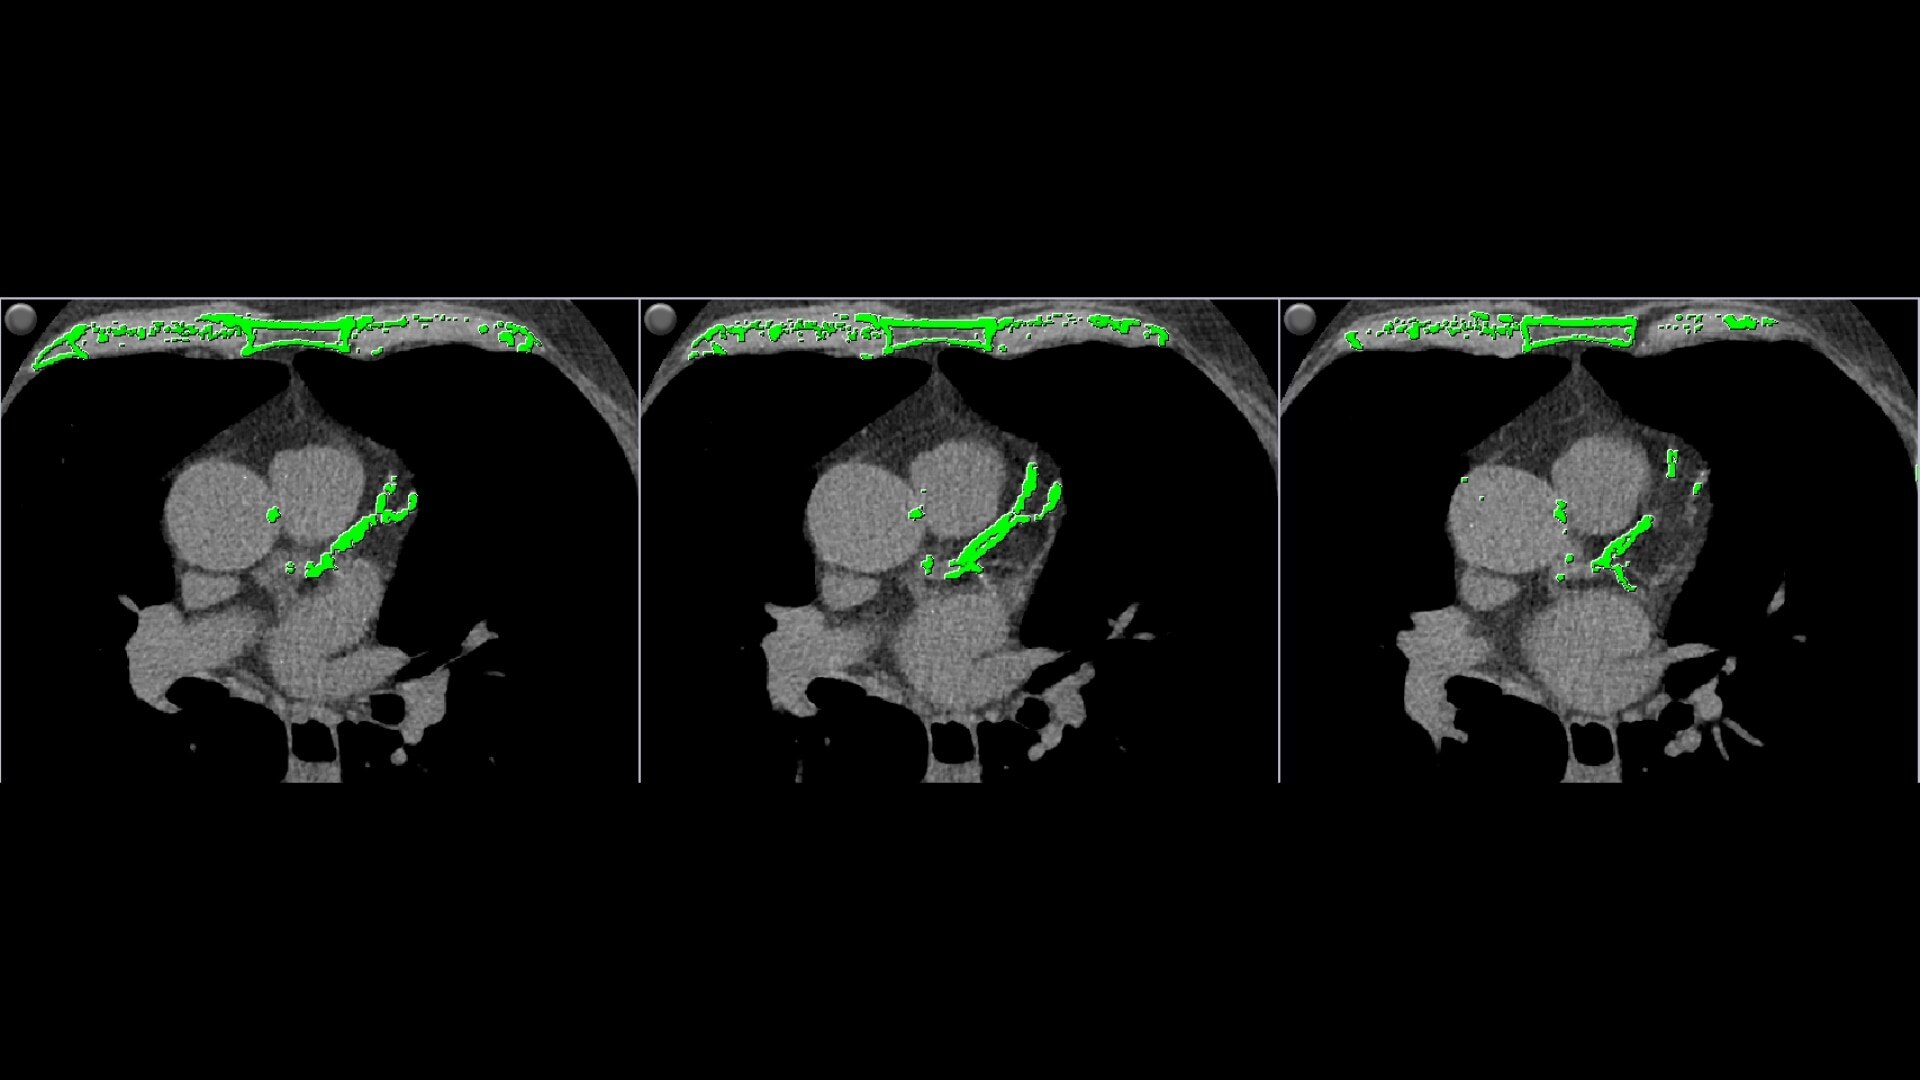

• Automatically detects calcium and highlights it in green

Automatic calcium detection and highlighting.